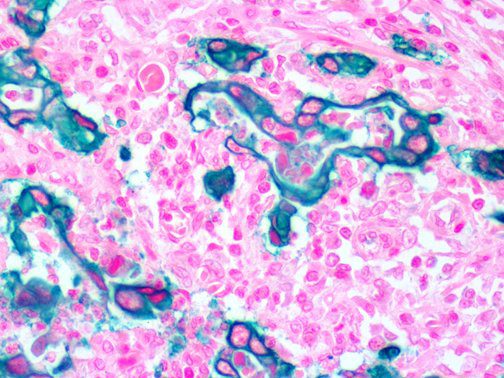

This activation induces inflammatory monocytes to highly express IL-6, starting a localized and then systemic cascade effect that results in hyperproduction of IL-6, which accelerates the inflammatory process. Because IL-6 also increases vascular permeability, excessive levels cause blood vessels to become very leaky. This, along with clotting factors released from vascular endothelial cells, stimulates the coagulation cascade, resulting in microthrombosis (tiny clots), which leads to ischemia and tissue death of the kidney, intestines, heart, liver, brain and extremities.